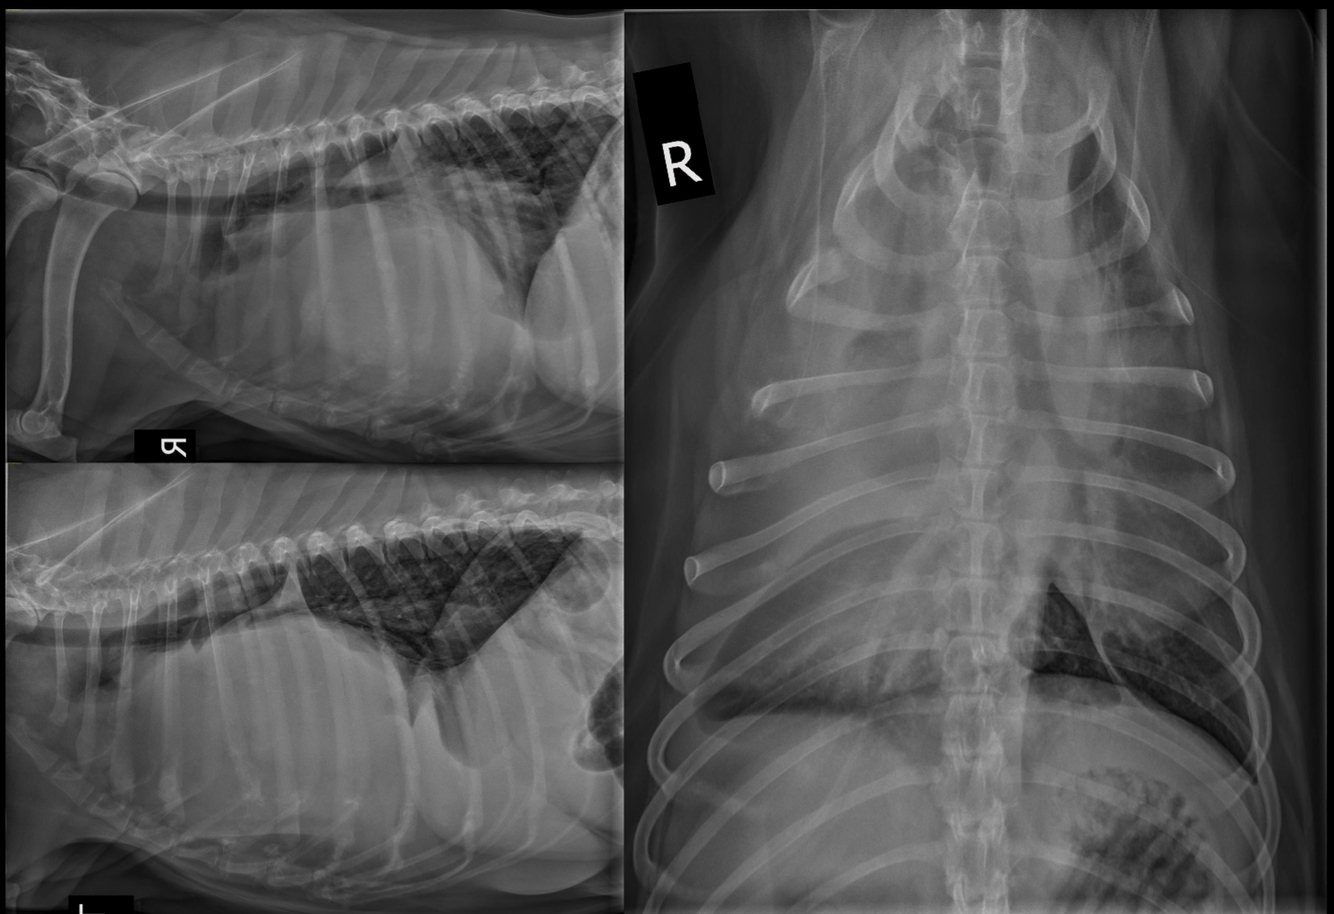

What is seen in these thoracic radiographs?

A

• sternal lysis and collapse with soft tissue swelling

• multiple, small pulmonary nodules

• osteolytic diaphysis and osteophyte formation